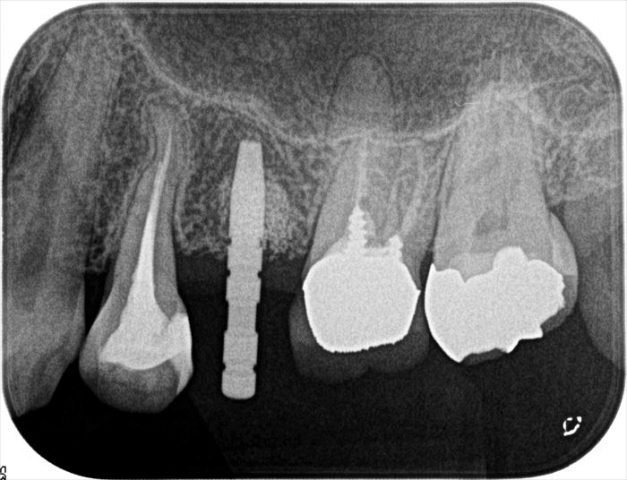

深度ゲージを挿入してレントゲンを撮影します。

レントゲン写真です。

予定通りの位置・角度にドリリング出来ていますのでドリルステップを進めていきます。

上顎洞底が拳上されて、テント状になっていることがよく分かるレントゲン写真です。

拳上された部分は穏やかに骨化していくと考えられています。